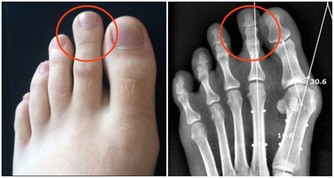

第一道坎、30~50歲:腸胃疾病關

據世界衛生組織統計,胃病的發病率高達80%,且發病呈年輕化趨勢。

30~50是生存壓力最大的時候,上有老、下有小,還要背負社會的壓力。

這個年齡段的人最容易患上胃病(消化不良、慢性胃炎等)、炎症性腸病(如潰瘍性結腸炎等) 疾病。

飲食不規律,愛吃熏烤、高鹽、辛辣食物,又嗜愛菸酒,這些不良習慣都會破壞胃腸道的正常功能,

嚴重損傷胃黏膜,導致腸胃疾病,也增加了癌變機率。